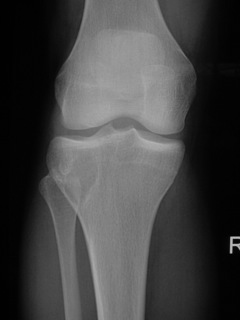

• Lytic lesion (Fig. 1, Fig. 2 & Fig. 3)

• Well-defined

• Geographic margins

• Eccentric

• Majority have well-defined sclerotic rims

• More aggressive lesions may have irregular margins

• Frequently produce endosteal erosion and cortical thinning

• Trabeculation may be seen

• In long bones, metaphysis, epiphysis, or diaphysis may be involved

Fig. 1

Fig. 1-3: AP and Lateral plain x-rays of a benign fibrous histiocytoma shows an eccentric lytic lesion in the proximal tibia, well- demarcated with a prominent sclerotic rim. No soft tissue mass or trabeculations are seen.